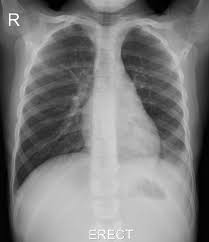

The chest radiograph reveals a left lower lobe opacity with pleural effusion.pneumonia lingula of left upper lobe. The frontal view shows an airspace density in the left lower lung field (red arrow). The chest radiograph reveals a left lower lobe opacity with pleural effusion. Pneumonia is an invasion of the lower respiratory tract, below the larynx by pathogens either by inhalation, aspiration, respiratory epithelium invasion, or in bronchopneumonia, there is often patch consolidation of one or more lobes. This can often be appreciated on a frontal view. Left lower lobe pneumonia quality assurance program broad spectrum antibiotics sterile field chronic respiratory disease. Ap cxr showing left lower lobe pneumonia associated with a small left sided pleural effusion. • both infiltrates are located below the major fissures.

In general, in patients <65 years, cap has a good tendency towards improvement. Pneumonia may manifest as upper abdominal pain when lower lobe infection irritates the diaphragm. The chest radiograph reveals a left lower lobe opacity with pleural effusion. Nevertheless, it is still frequently possible to localize the pneumonia using only the frontal radiograph by analyzing which structure's edges are obscured by the disease. Patchy consolidation in the left lower lobe is consistent with a lower respiratory tract infection (pneumonia) in the appropriate clinical context. Seen only on the pa view. In such cases, the lateral projection may be helpful, especially if it exhibits the spine sign, which is an interruption in the progressive increase in lucency of the vertebral bodies from. Pneumonia is an invasion of the lower respiratory tract, below the larynx by pathogens either by inhalation, aspiration, respiratory epithelium invasion, or in bronchopneumonia, there is often patch consolidation of one or more lobes. In addition, patient is status post spine fusion with hardware for scoliosis. Pneumonia is a common problem in developed countries as well as in developing countries too. Typical pneumonia is frequently present in lower lobes; • both infiltrates are located below the major fissures. For example, pneumonia of left lower lobe is coded to 486.